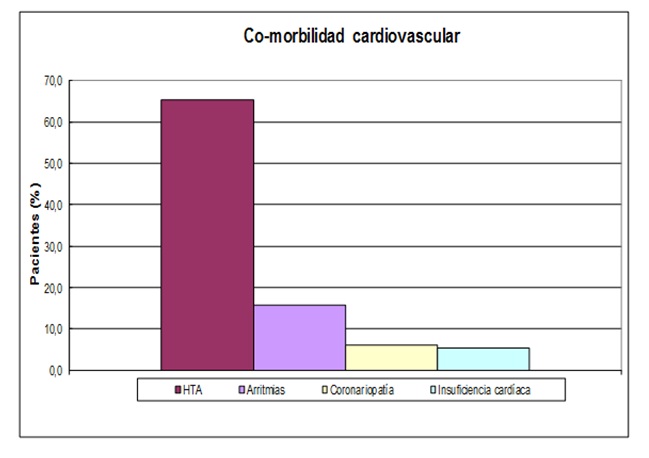

Se presentan los antecedentes de trastornos cardiovasculares en los pacientes con historia clínica electrónica. La hipertensión arterial sistémica fue un hallazgo frecuente en los pacientes referidos por SAHOS (65,2%). Le siguen en frecuencia las arritmias (15,7%), coronariopatía (6,1%) e insuficiencia cardíaca (5,4%). (Figura 10).

Figura 10: Porcentaje de pacientes con antecedentes cardiovasculares (n=447). HTA: hipertensión arterial sistémica.